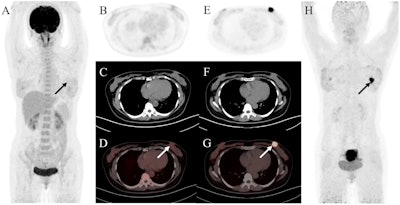

A 47-year-old woman was admitted with a left breast mass. For staging, the patient underwent F-18 FDG-PET/CT. The maximal intensity projection image (A) and the axial views (B: PET image; C: CT scan; D: PET/CT fused image) revealed normal findings. Then she underwent Ga-68 FAPI-PET/CT. The left breast showed intense uptake on Ga-68 FAPI-PET/CT (E: PET image; F: CT scan; G: PET/CT fused image; H: MIP, solid arrow; SUVmax, 15.4). Subsequently, the patient underwent pathology confirmed invasive lobular carcinoma of the left breast. Image and caption available for republishing under Creative Commons license (CC BY 4.0 DEED, Attribution 4.0 International) and courtesy of Cancer Imaging.

A 47-year-old woman was admitted with a left breast mass. For staging, the patient underwent F-18 FDG-PET/CT. The maximal intensity projection image (A) and the axial views (B: PET image; C: CT scan; D: PET/CT fused image) revealed normal findings. Then she underwent Ga-68 FAPI-PET/CT. The left breast showed intense uptake on Ga-68 FAPI-PET/CT (E: PET image; F: CT scan; G: PET/CT fused image; H: MIP, solid arrow; SUVmax, 15.4). Subsequently, the patient underwent pathology confirmed invasive lobular carcinoma of the left breast. Image and caption available for republishing under Creative Commons license (CC BY 4.0 DEED, Attribution 4.0 International) and courtesy of Cancer Imaging.